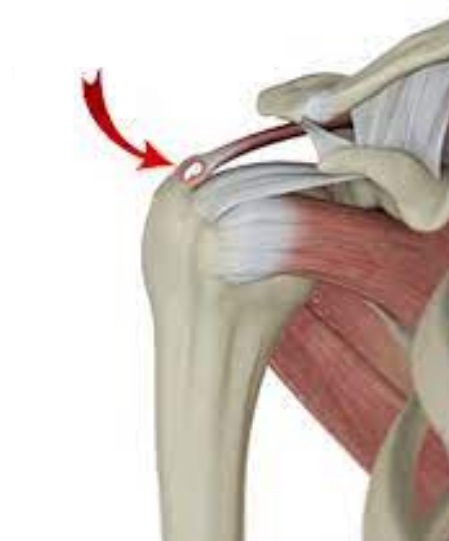

석회성 힘줄염은 통증이 자연스럽게 사라지는 경우도 있지만, 방치하면 만성 통증으로 이어지거나 어깨 힘줄 파열로 진행될 수 있으니 꼭 전문가의 진료를 받아보는 게 중요해요.

| 수술적 치료 | 비수술적 치료에 효과가 없거나 석회 크기가 너무 클 경우, 관절내시경으로 석회를 제거합니다. |